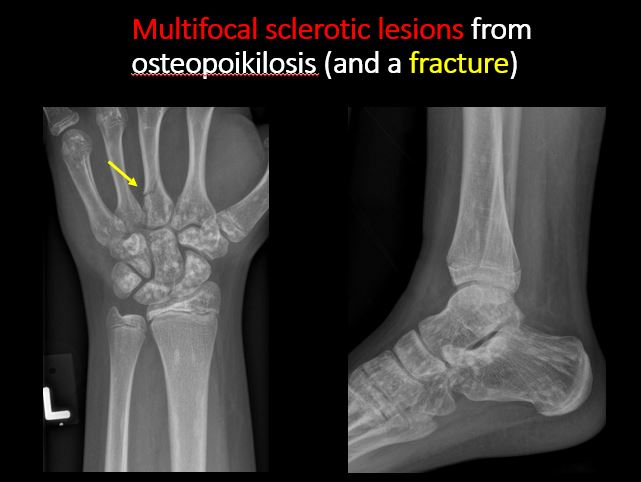

There is/are focal or multifocal lytic/lucent, blastic/sclerotic or mixed density lesion(s) or other abnormality. |

No | NA |